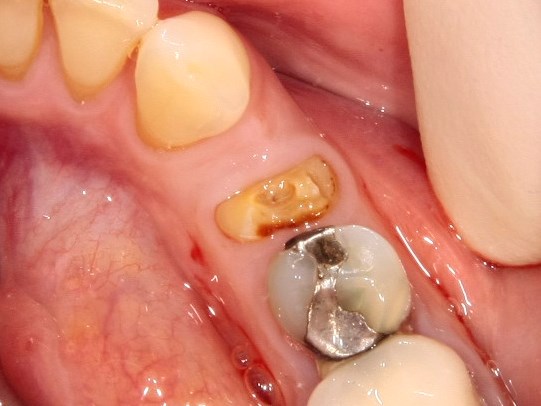

Немедленная имплантация — оптимальное решение в любой клинической ситуации